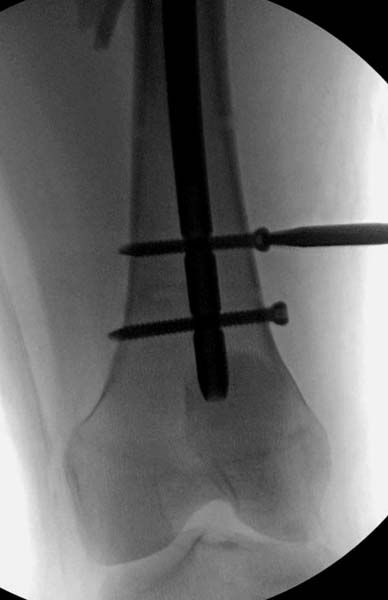

> стабильная.. На третьий день провели стабилизацию перелома бедра

> антеградным остеосинтезом.

> Закрытый БИОС решает множественные проблемы связанные с лечением

> переломов, но проблема дистальной блокировки без рентгена до сих пор

> остается нерешенной. Рекламированные производителями приспособления для

> дистальной блокировки из-за различной кривизны кости не эффективны или

> стоит очень дорого (Smith&Nephew SureLock). Задержка операции из-за

> блокировки не всегда удовлетворяет, и многих вынуждает искать